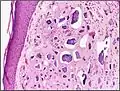

Histopathology of calcinosis cutis in human tissue